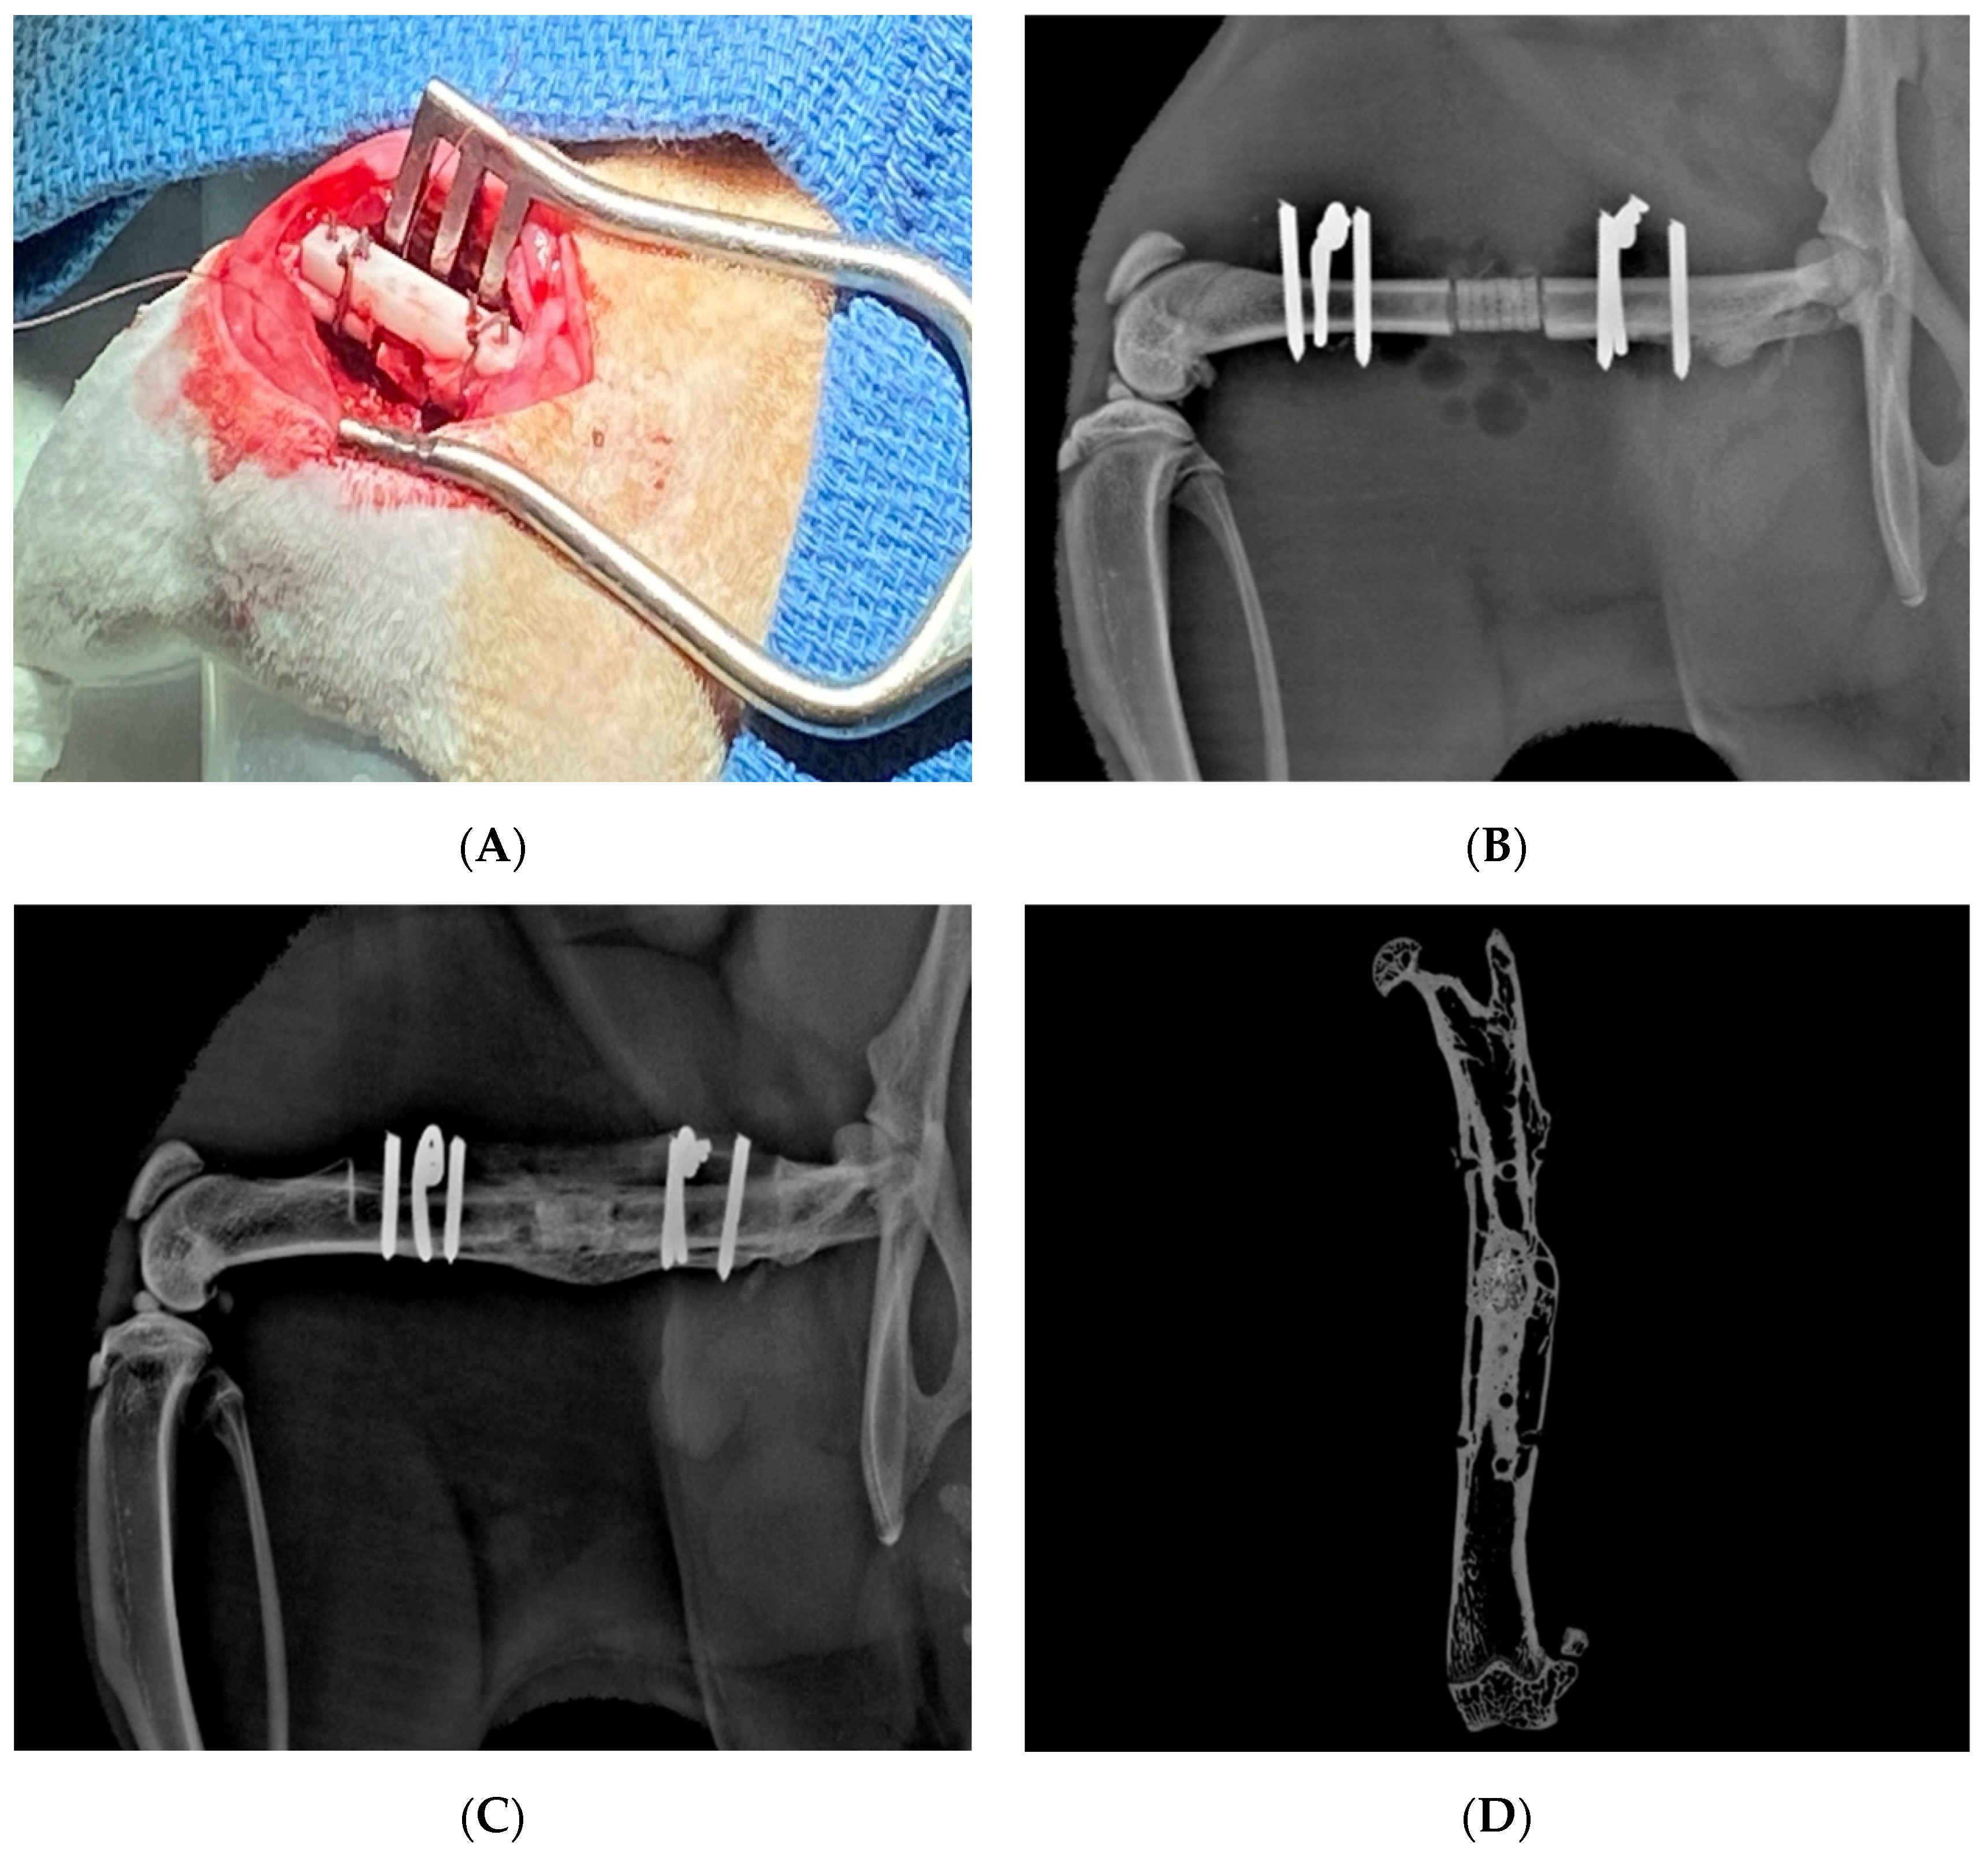

2.1.3. Vascularized Bone Grafting